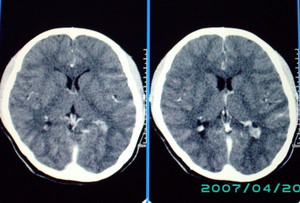

以下是引用九目段在2007-12-24 14:55:00的发言:[br]1,年轻女性[br]2,ct表现:左侧脑室三角区可见一不规则小明显强化的结节,中央见小低密度,侧脑室无扩张。[br]分析:[br]常见的有三种肿瘤好发三角区:[br]1,脉络丛乳头状瘤,好发于年轻者,明显强化,实性,分泌脑脊液,常伴有侧脑室扩大,肿瘤较小可以脑室扩大不明显,不能排除,但小结节尚不易形成坏死腔。[br]2,室管膜瘤,好发于儿童及青少年,明显强化,易坏死,大时伴脑室扩张。[br]3,脑膜瘤,明显强化,圆形,界请,无脑积水,一般不坏死。[br]诊断:[br]左侧脑室三角区结节,考虑室管膜瘤可能性大,不排除脉络丛乳头状瘤和脑膜瘤(因病史较长)。[br][br][本贴已被 九目段 于 2007-12-24 15:13:35 修改过]